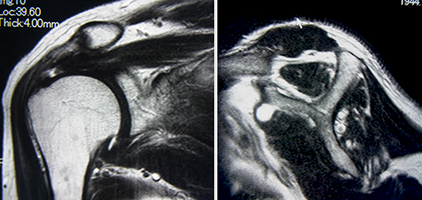

修復可能な腱板断裂。腱の断端は少ししか短縮していない。

筋肉はわずかに白い脂肪に置き換わっているのみである。

修復不能腱板断裂。腱板断裂は大きく内側に短縮している。

筋肉は小さくなり、大部分が白い脂肪組織に置き換わっている。